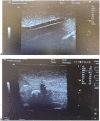

Ultrasound-guided vascular access is a medical procedure that is becoming increasingly common in daily practice and is recommended to avoid iatrogenic complications. One of the procedures with a high-risk rate of complications is the vascular puncture. However, training on this technique can be challenging due to the limited availability of simulation models. We propose a simple, cost-effective, and effective ultrasound-guided vascular access simulation model that utilizes chicken breast and a urine catheter to address this need.